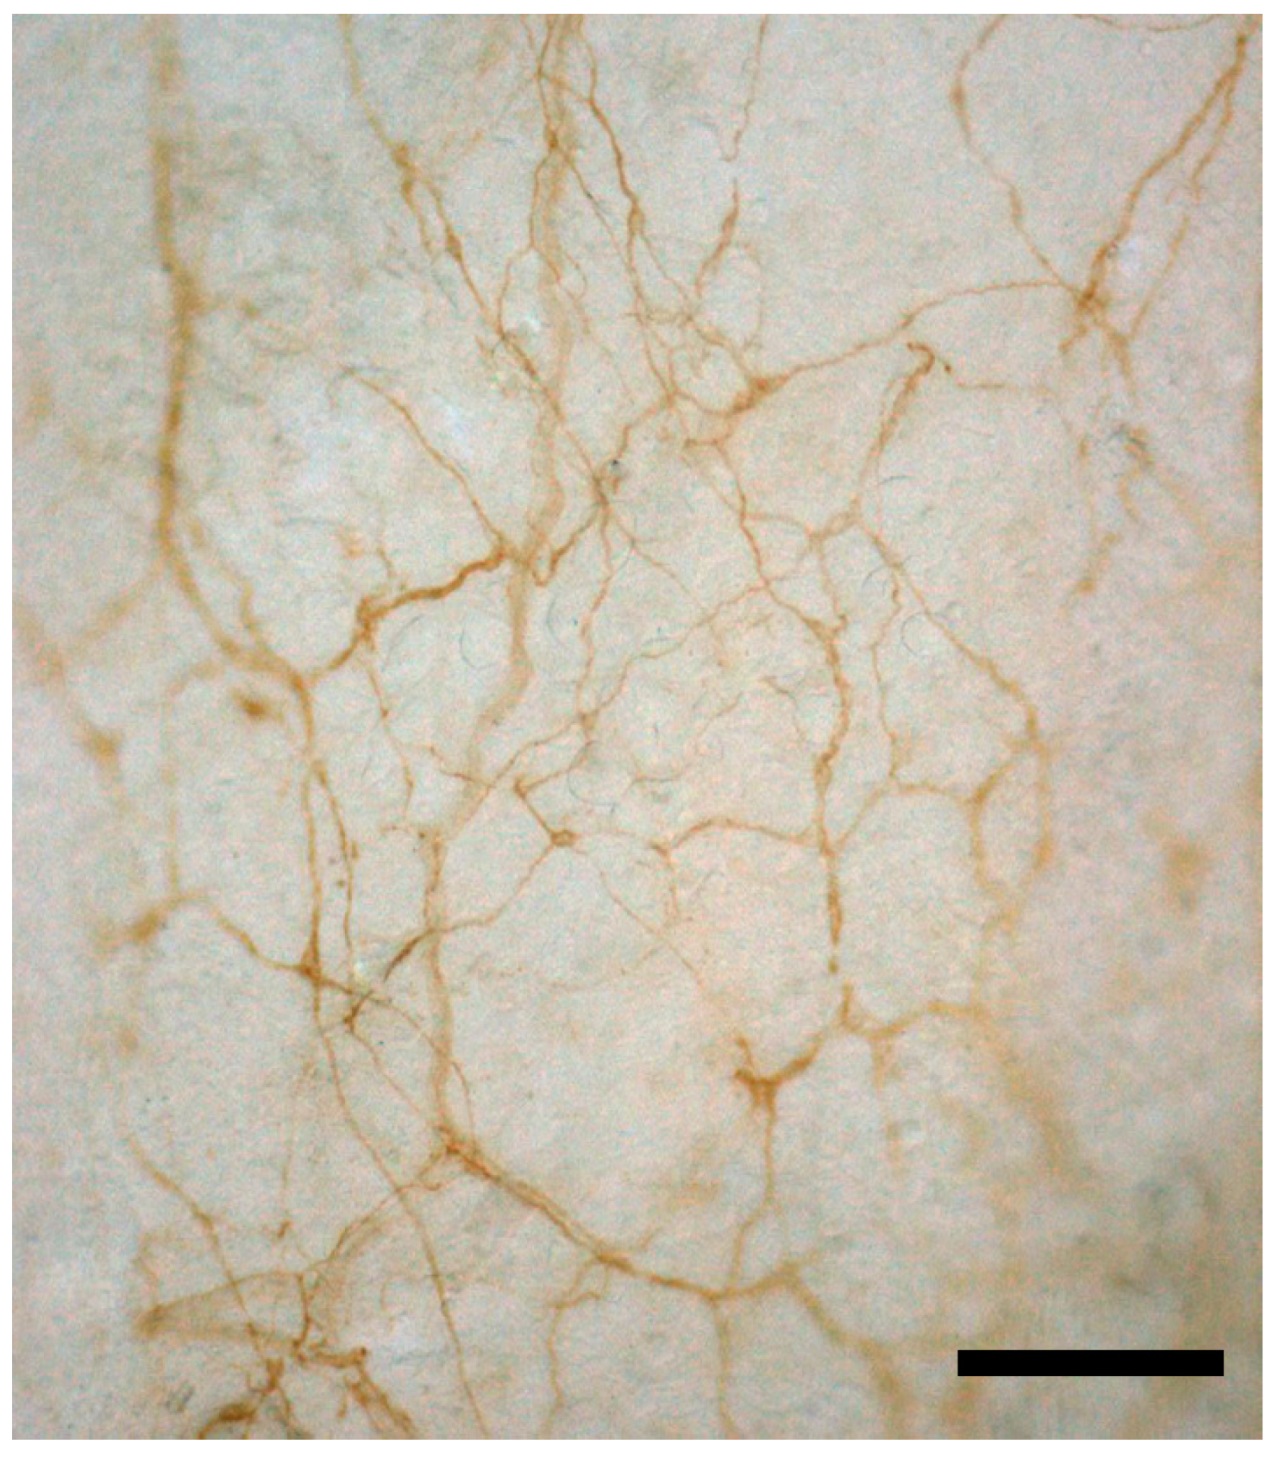

▲ 小鼠胸腰筋膜的神經(jīng)網(wǎng)絡(luò)